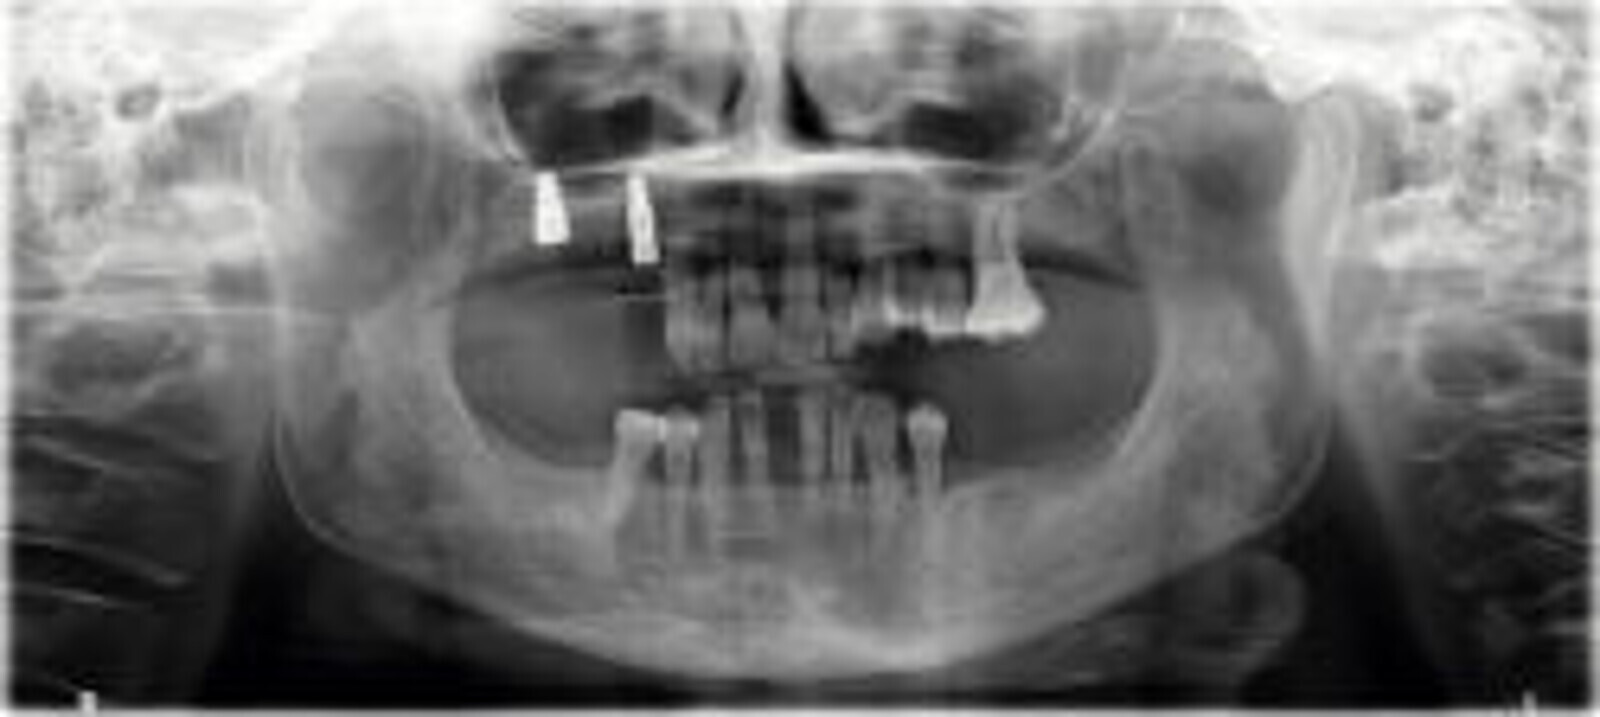

Slika 3. Inicijalni rendgenski nalazi prije početka liječenja.

58-godišnjakinja, nepušačica i sistemski zdrav pacijent kojeg je njen doktor dentalne medicine uputio u naš centar radi implanto-protetske terapije. Pacijenticu je uglavnom smetala loša estetika u gornjem frontalnom području, koje je karakterizirala visoka linija osmijeha i izražene anomalije položaja zuba (Slike 1. i 2.), kao i funkcionalna ograničenja kao posljedica neugode prilikom žvakanja. Tri zuba su nedostajala u gornjoj distalnoj regiji i to zubi 17, 15 i 27 koji nisu bili protetski opskrbljeni, dok je u donjoj čeljusti u distalnoj regiji nedostajalo pet zuba s obje strane u području premolara te su oni zamijenjeni djelomičnom mobilnom protezom. Svi preostali zubi u gornjoj i donjoj čeljusti bili su prema klasifikaciji „Proceedings of the World Workshop on the Classification of Periodontal and Peri-implant Diseases and Conditions 2017“ imali parodontitis stadija IV, a prosječna dubina sondiranja parodonta je bila 5,6 mm. 7 Prosječni indeks krvarenja (BOP) i srednji indeks plaka (PI) bili su 70 odnosno 80 posto. S obzirom na paradontološke parametre i mjere oralne higijene (vidljivi kamenac i naslage), oralna higijena pacijentice klasificirana je kao loša. Pacijentica je u drugoj ordinaciji liječena s dva implantata u desnoj maksilarnoj stražnjoj regiji kako bi se zamijenili prvi pretkutnjak i prvi kutnjak (Slika 3). Prema definiciji koju je Weißgold uveo 1977. godine, pacijent ima debeli biotip. 26

U regijama dva lateralna maksilarna sjekutića 12 i 22 prema uputama iz „Proceedings of the Fourth ITI Consensus Conference (Chen et al., 2009)“ i očuvanjem grebena u lijevoj premolarnoj regiji (zubi 24 i 25) uporabom dentinskog grafta, dobivenog od dva izvađena lijeva maksilarna premolara. Zbog povećanog stupnja nestabilnosti zuba i jer se pomoću digitalne volumenske tomografije (CRANEX 3D Ceph, Soredex, KaVo Kerr) pokazalo da je bukalna kost vrlo tanka procijenjeno je da dva središnja maksilarna sjekutića 11 i 21 nisu prikladna za „Socket Shield“ tehniku (Slika 4). Umjesto toga, planiran je RST za oba sjekutića, kako bi se spriječila resorpcija bukalne koštane lamele i gubitak volumena alveolarnog grebena kao posljedica vađenja zuba.